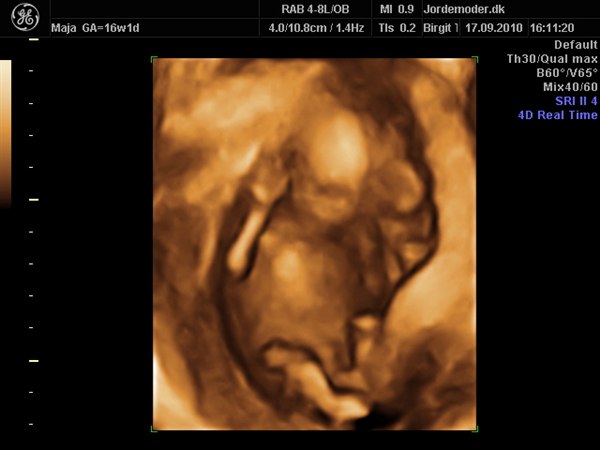

Vi var i fredags til scanning hvor jeg var 16+1 og det var en super fed oplevelse, selvom den lille var genert

vi ønsker ikke at vide kønnet, så er jo dejligt vi alligevel kunne få lov at opleve 3D

Vedhæftede fotos (klik for at se i fuld størrelse)